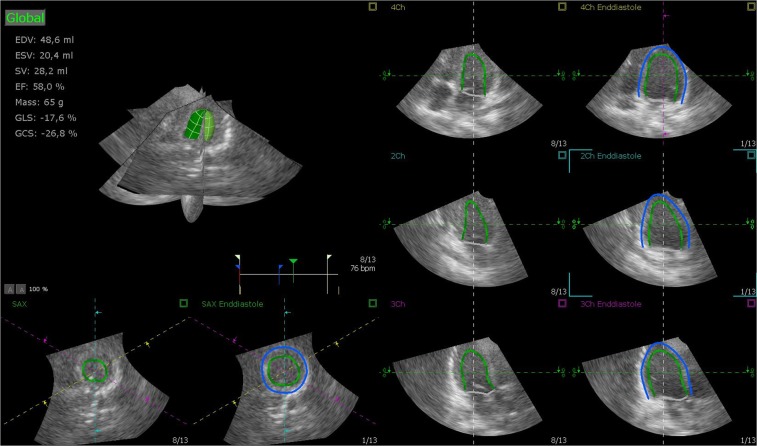

Figure 4.

Sample images of the heart by RT3DE (software Tomtec). Two-dimensional slices from a representative real-time 3D echocardiographic data set with endocardial (green) and epicardial (blue) borders of the left ventricular myocardium.